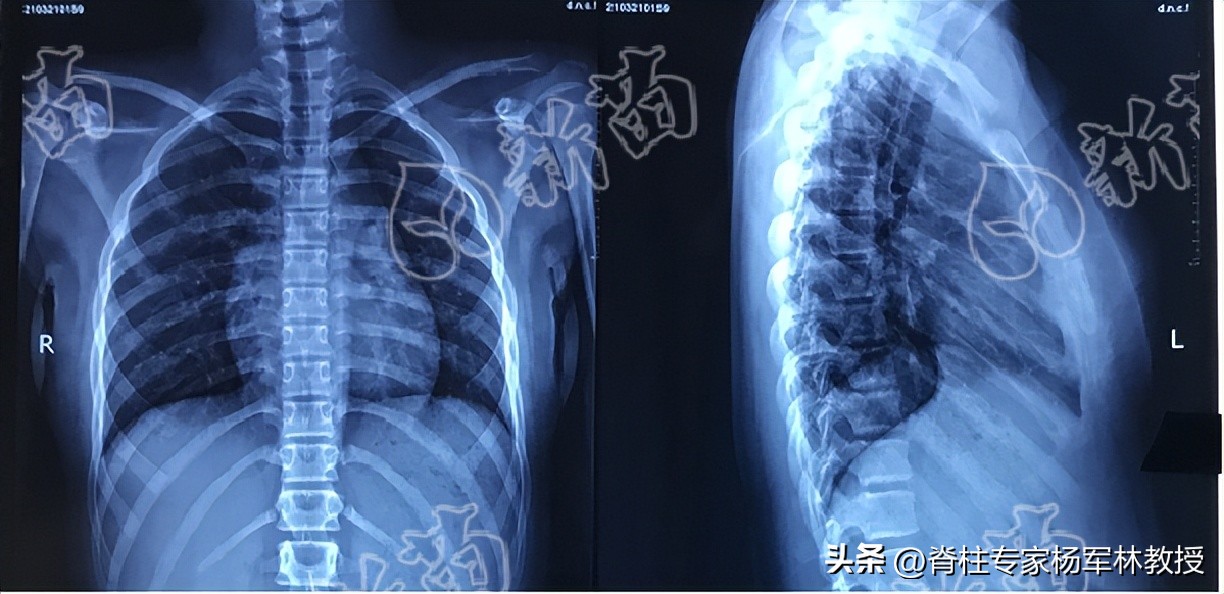

X光片为什么不能只拍半截?

拍摄包含颈、胸、腰椎的全脊柱正侧位X光拼图,才能完整评估脊柱的弯曲状态。

若只有半截脊柱的X光片,只提示部分脊柱的影像学信息,不便于医生的准确判断。

图片源自:新苗团队

非全脊柱拼图的半截脊柱X光片仅能作为评估脊柱侧弯病情的参考,想要得到准确诊断,还是建议拍摄正确的全脊柱X光片。